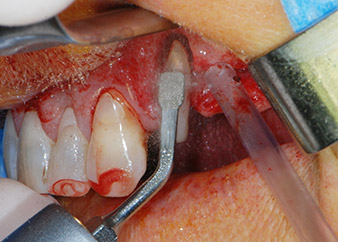

Un mes después, en el día de la intervención, el dolor y la inflamación se habían reducido al mínimo en la pieza 24, pero seguía habiendo una movilidad de clase II de Miller. Después de la apertura de los colgajos y de la limpieza del tejido infectado periapical y perirradicular, la extensión del defecto óseo quedó evidente (figuras 2 y 3).

En la raíz bucal, faltaba todo el hueso vestibular y distal. Básicamente, la fijación se limitó a la raíz palatal, lo que corroboró el mal pronóstico preliminar. La pieza 27 también mostró una fijación horizontal reducida (figura 12) y una rarefacción apical mínima (figura 1), si bien sin síntomas clínicos.

En primer lugar, en un intento por gestionar el problema endo-periodontal, el resto de la superficie radicular se desbridó con cuidado con un equipo piezoeléctrico (Piezomed de W&H, utilizado con el inserto S1 con forma de espátula, concebido en un principio para la erosión de la pared lateral del seno) (figura 4). A continuación, el ápice se erosionó con el mismo instrumento para eliminar el tejido apical infectado residual y reducir las posibles ramificaciones accesorias del canal radicular (apicectomía) (figura 5). No fue necesario realizar un retrorellleno, puesto que la obturación ortógrada se acababa de revisar.